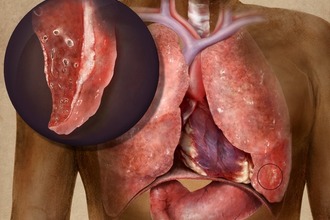

Рак легкого

Рак легкого проявляется различными болями. В зависимости от расположения опухоли, ее распространенности и стадии болезни, боль может быть ноющей или опоясывающей. Чаще всего она постоянная и усиливается при кашле. Если вовлекаются ребра и позвоночник, дискомфорт становится более выраженным.

Дополнительные симптомы, такие как длительный кашель, общее недомогание, субфебрильная температура и боли в грудной клетке, требуют проведения дополнительных исследований для уточнения диагноза. Современные аппаратные методы помогут точно определить локализацию и характер поражения.